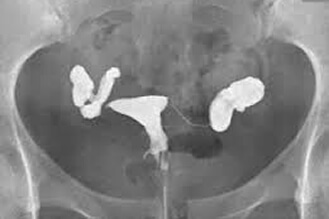

正常輸卵管攝影,雙側輸卵管通暢